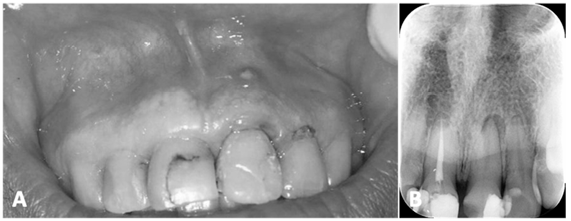

Paciente masculino, com 62 anos de idade, hipertenso, dirigiu-se ao serviço odontológico com queixa de surgimento de uma bolha na região vestibular dos dentes anteriores e superiores. Relatou perceber a saída eventual de líquido de cor amarelada e gosto ruim. Referiu, ainda, fazer uso diariamente de losartana 50 mg e metformina 500 mg. Ao exame físico, foram observadas restaurações nos dentes anteriores e a presença de fístula na região relacionada ao ápice do dente 21, conforme imagens A e B a seguir. No exame radiográfico, foi possível observar: o dente 12 com restauração na mesial; o dente 11 com restaurações extensas e com tratamento endodôntico; o dente 21 com restauração distovestibular e aspecto de rarefação óssea periapical; e o dente 22 com restauração mesial.

Imagem A: imagem intrabucal da região vestibular superior evidenciando a presença de restaurações nos dentes 11, 12, 21 e 22; dente 21 com imagem de inflamação na região gengival com presença de fístula na região apical. Imagem B: radiografia periapical da região evidenciando dente 12 com restauração na mesial; dente 11 com restaurações extensas e com tratamento endodôntico; dente 21 com restauração distovestibular e aspecto de rarefação óssea periapical; e dente 22 com restauração mesial.